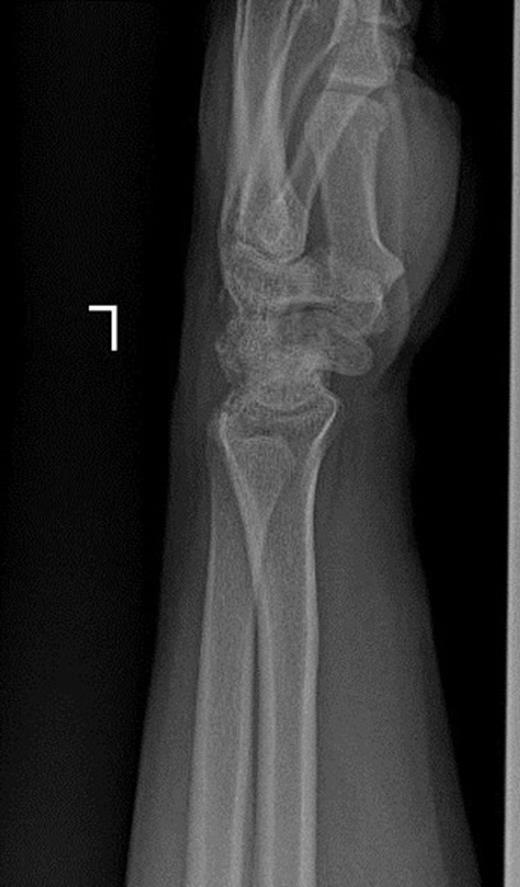

Pins were removed six weeks later, and the cast was discarded ten weeks later. Active and passive range of wrist motion and muscle strengthening exercises were begun. The patient didn’t refer for follow-ups. After two years, he came back with pain, limited motion, and weakness in grip and grasp. Radiographs showed osteonecrosis of lunate and proximal scaphoid. Also, static scapholunate dissociation with signs of mild arthritis was obvious (Figure 2a & 2b).

Posteroanterior and lateral radiographs of left wrist two years after operation show increased density of lunate and proximal scaphoid with subtle arthritic changes. Scapholunate dissociation (Terry-Thomas sign) and dorsal intercalated segment instability are seen.